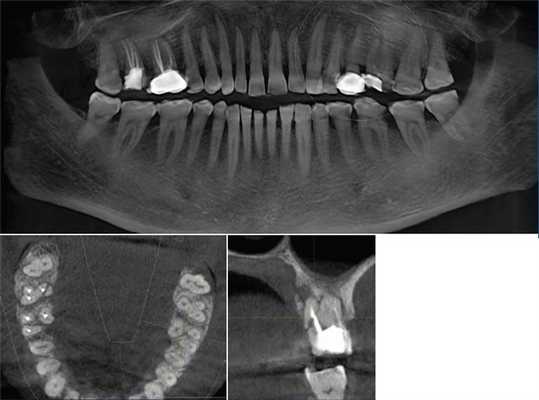

(Слева) На кадрированной панорамной реформатированной КЛКТ визуализируется импактный третий моляр в области угла нижней челюсти. Четко визуализируется ПЗ, связанный с верхним краем фолликула. ПЗ рассматривается как тракт, по которому зуб проходит к обычному месту прорезывания в альвеолярном отростке. Обратите внимание на сдавление нижнечелюстного канала снизу.

(Справа) На профильном срезе КЛКТ у этого же пациента визуализируется проводник зуба.